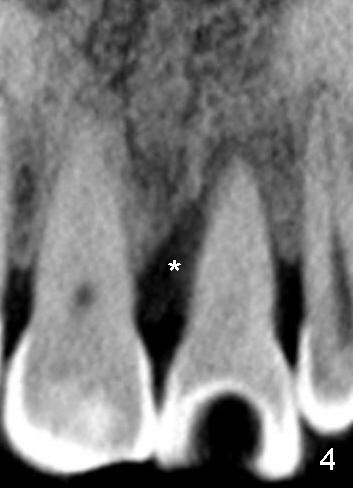

A 60-year-old lady had an abscess mesial to #9 six years ago (Fig.1,2 <), treated as a perio lesion by laser (Fig.3) and osseous surgery without bone graft (Fig.6, followed by CT exam revealing semi-circumferential bone loss (Fig.4,5). When the perio treatment failed, attention was paid to endo aspect (Fig.7-9). In fact the pulp was found to be vital when access to root canal therapy was made. As expected, the treatment failed again. The palatal fistula persisted. The infection was suspected to be a source of remote immediate implant site (#30). The tooth #9 was extracted. It appears that there is a semilunar crack line in the linguomesial root (Fig.12). When the socket healed 2 weeks post extraction (Fig.10), the #30 buccal defect was debrided with bone graft. There was no bone resorption 4 weeks post extraction (Fig.11); a 4.5x17 mm implant was placed (Fig.13-15). An immediate provisional was fabricated (Fig.16-18). Fig.19,20 were taken 3 months post implantation and 7 months post cementation, respectively. Dense bone forms around the implant coronally 4 years 5 months post cementation (Fig.21), while the gingiva is healthy palatally (Fig.22) and buccally (Fig.23).